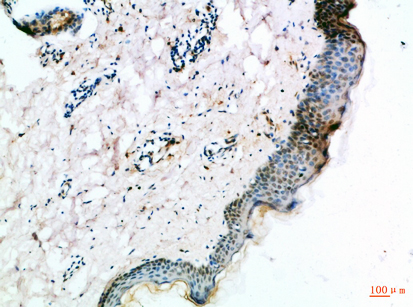

Immunohistochemistry

IHC (Immunohistochemistry)

The FZD4 fzd4 (Catalog #AAA296639) is an Antibody produced from Rabbit and is intended for research purposes only. The product is available for immediate purchase. The Frizzled-4 Polyclonal Antibody reacts with Human, Mouse, Rat and may cross-react with other species as described in the data sheet. AAA Biotech's Frizzled-4 can be used in a range of immunoassay formats including, but not limited to, IHC (Immunohistochemistry). Researchers should empirically determine the suitability of the FZD4 fzd4 for an application not listed in the data sheet. Researchers commonly develop new applications and it is an integral, important part of the investigative research process. It is sometimes possible for the material contained within the vial of "Frizzled-4, Polyclonal Antibody" to become dispersed throughout the inside of the vial, particularly around the seal of said vial, during shipment and storage. We always suggest centrifuging these vials to consolidate all of the liquid away from the lid and to the bottom of the vial prior to opening. Please be advised that certain products may require dry ice for shipping and that, if this is the case, an additional dry ice fee may also be required.Precautions